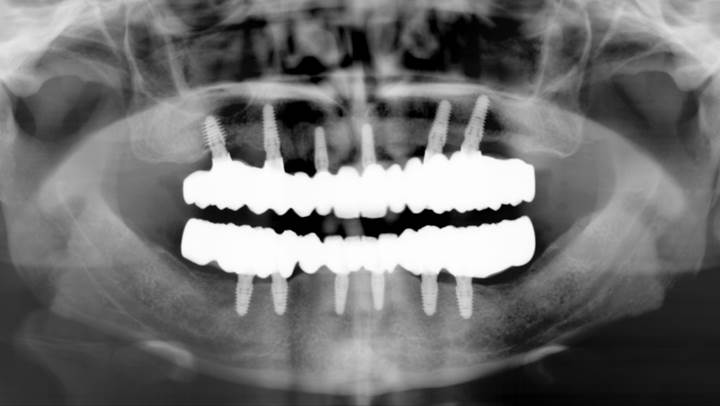

Clinical case: Extraction of all teeth in upper maxilla,

immediate implant placement, & provisionalization

- Courtesy of Dr. Iulian Filipov, Romania -

Keywords

AnyRidge, immediate placement, immediate provisionalization, maxillary fully edentulous case, initial stability, edentulous, Dr. Iulian Filipov, R2GATE, MEGA ISQ

Products:

AnyRidge implant system, Mega ISQ, R2GATE